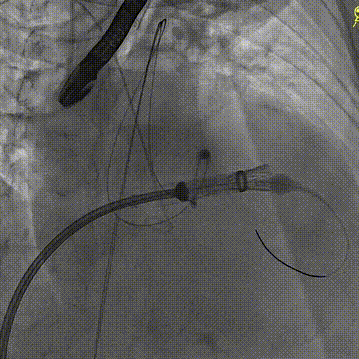

随后在超声引导下进行房间隔穿刺,最终穿刺高度约3.4cm,顺利建立经房间隔入路。而后沿成环导丝于二尖瓣环下植入固定环,通过DSA及3D超声确认固定环完全关闭且位置合适。沿股静脉送入HighLife TSMVR瓣膜,首先释放瓣膜心室端,随后牵拉输送器,超声下观察,使瓣膜心室端与固定环充分贴合,旋即保持拉力并释放瓣膜心房端,人工瓣膜脱钩,在固定环的辅助下,于二尖瓣瓣环平面完成自同轴,最后逐步撤出人工瓣膜输送系统和固定环输送系统。即刻超声评估提示二尖瓣返流完全消失,无瓣周漏,人工瓣膜植入位置理想,形态良好,跨瓣压差1mmHg;LVOT压差6mmHg,无左室流出道梗阻风险;房间隔4mm左向右分流,无即刻封堵指征。手术成功完成!

固定环植入

固定环位置评估